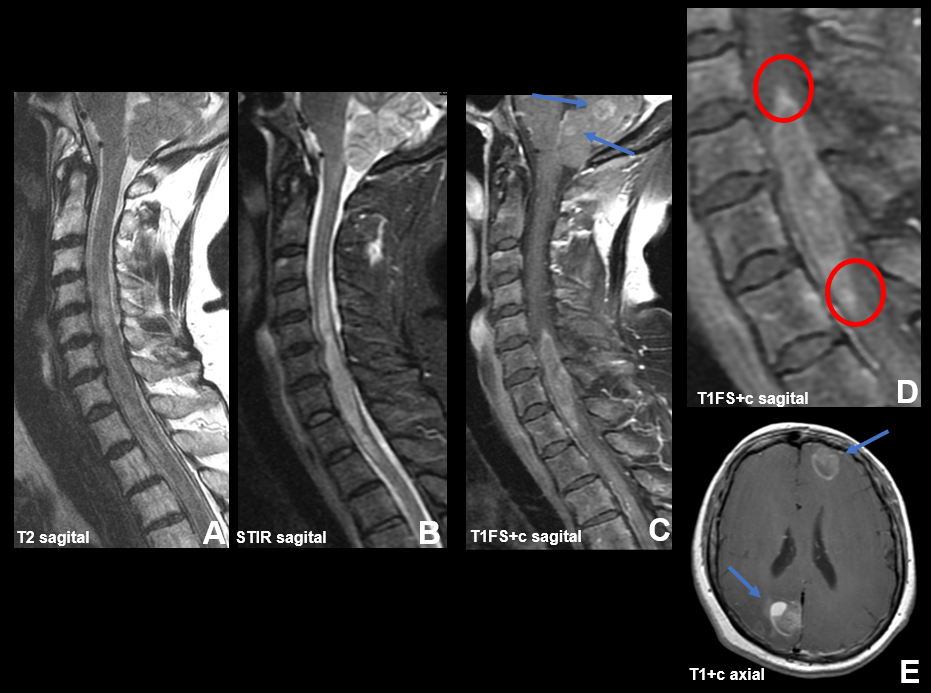

Resonancia magnética: secuencias ponderadas en T1 con gadolinio en plano axial (A), sagital (B) y coronal (C): Masa extraaxial de aspecto heterogéneo, bien definida, con un intenso realce periférico, de 42 x 41 x 38 mm (AP x TR x CC) en la línea media frontobasal. La lesión está en contacto con la lámina cribiforme y parece originarse del bulbo y tracto olfatorio izquierdo. Aisladas formaciones quísticas periféricas. Secuencia ponderada en T2 plano coronal (D): extensa área de hiperseñal T2 que se extiende por la sustancia blanca del lóbulo frontal izquierdo.